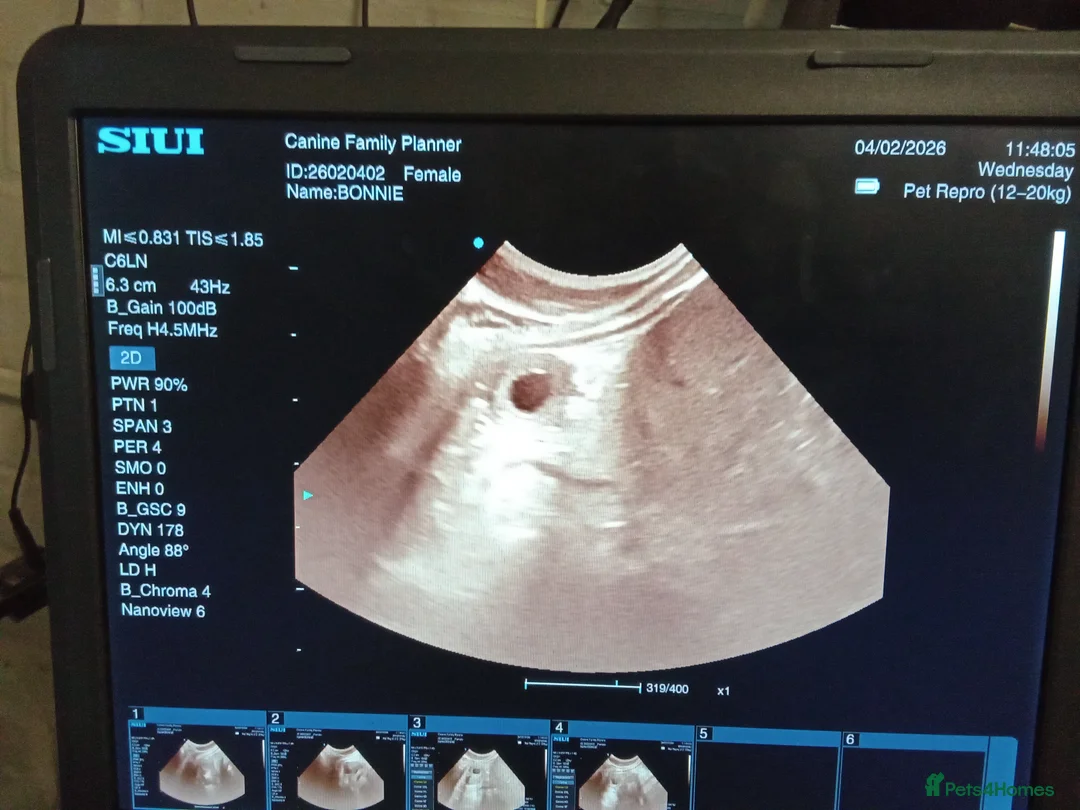

If you are planning a litter, one thing is clear: Health directly affects how comfortably your puppies are rehomed, and it influences the pregnancy and rearing experience from the very beginning. Sound, health-tested parents reduce avoidable stress. They support smoother pregnancies, stronger puppies and greater confidence for the families who will welcome them. Meet Luther. Proven, fertility-tested, and fully health-tested from seven generations of carefully bred Bulldogs. His first litter is due this March. KC registered and Crufts 2026 qualified, Luther represents the good breed type recognised in the show ring, with wins that reflect correct structure and balance. He offers a clean front, well-laid shoulder, compact outline and substance without exaggeration. Just as importantly, he has the steady, affectionate family temperament expected of the breed, calm, people-focused and reliable in the home. Luther's first litter of 4 (pictured) was born 16th March, all of excellent weights and have flourished since birth. Health That Builds Confidence • HUU (DNA) clear • BOAS (Breathing) graded • Patella (knees) graded • Silver Health Award • Fertility tested • No history of cherry eye, hernias or cleft palate in his immediate lineage • Base coat colour (DNA) is Pied (though he is mainly white) and will sire mainly marked Reds/Fawn with White Flexible Stud Terms - Payments by debit or credit card are accepted. • £100 handling fee payable at mating • Followed by £200 per live puppy, with the total fee capped at the equivalent of five puppies, regardless of litter size • Discounted fee for fully health-tested females • Chilled shipment available (approved veterinary practices only) • Stud dog travel is also considered Clear terms. Low upfront risk. Ongoing support. Luther is seriously worth considering. Instagram: @laroyal_bulldogs